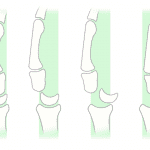

- Acute lunate dislocation with 90 degrees volar tilt and 1 cm volar displacement of the lunate

- Lunate dislocation

Acute lunate dislocation with 90 degrees volar tilt and 1 cm volar displacement of the lunate.

- Mayfield JK, Johnson RP, Kilcoyne RK. Carpal dislocations: pathomechanics and progressive perilunar instability. J Hand Surg Am 1980; 5(3): 226-241.